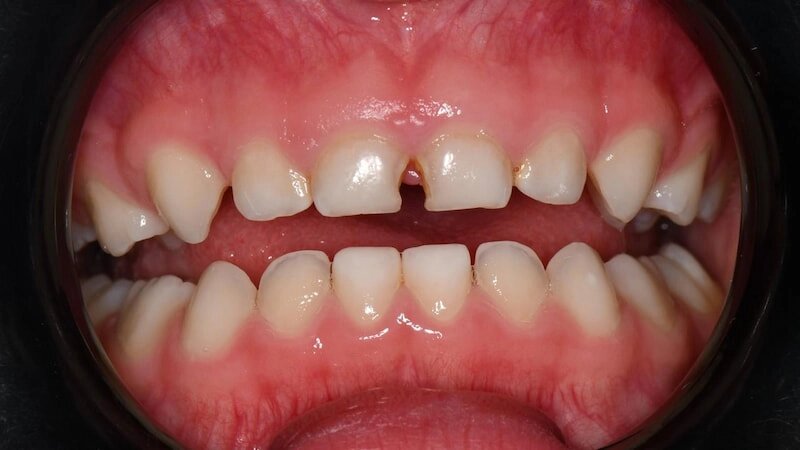

Так выглядят зубы, которые восстановили реставрациями/пломбами, спустя 2 года после лечения:

-13